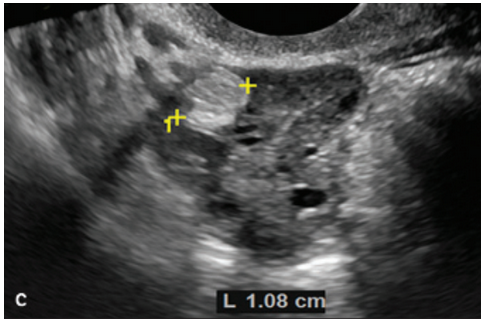

患者女,25 岁,发病 1 月内临床症状表现为精神行为异常、躁狂、谵妄、行为性格改变。脑脊液穿刺发现抗 NMDA 受体抗体,PET-CT、盆腔 MRI 增强扫查发现双侧卵巢无异常(图 1A),脑电图检查提示脑病待查。患者接受了为期 5 天的静脉内注射免疫球蛋白及琥钠甲强龙,病情加重,出现紧张综合症、自主神经功能障碍等,遂转至重症监护病房。随后行经阴道超声检查,发现双侧卵巢形态大小正常,右侧卵巢内探及一大小约 13×11×10 mm 囊实性回声肿块,左侧卵巢内探及范围约 6×5×5 mm 高回声区,考虑双侧卵巢畸胎瘤 ( 图 1B-D)。

图 1 抗 NMDA 受体脑炎伴卵巢畸胎瘤:图 A 为盆腔 MRI T2WI,见双侧卵巢形态大小、位置正常;图 B 为经阴道超声矢状切面声像图,右侧卵巢内见混合囊实性肿块(星号);图 C 为经阴道超声冠状切面声像图,右侧卵巢内见异常高回声区;图 D 为经阴道超声矢状切面声像图,左侧卵巢内见大小约 5.0×5.8 mm 高回声灶,考虑小畸胎瘤